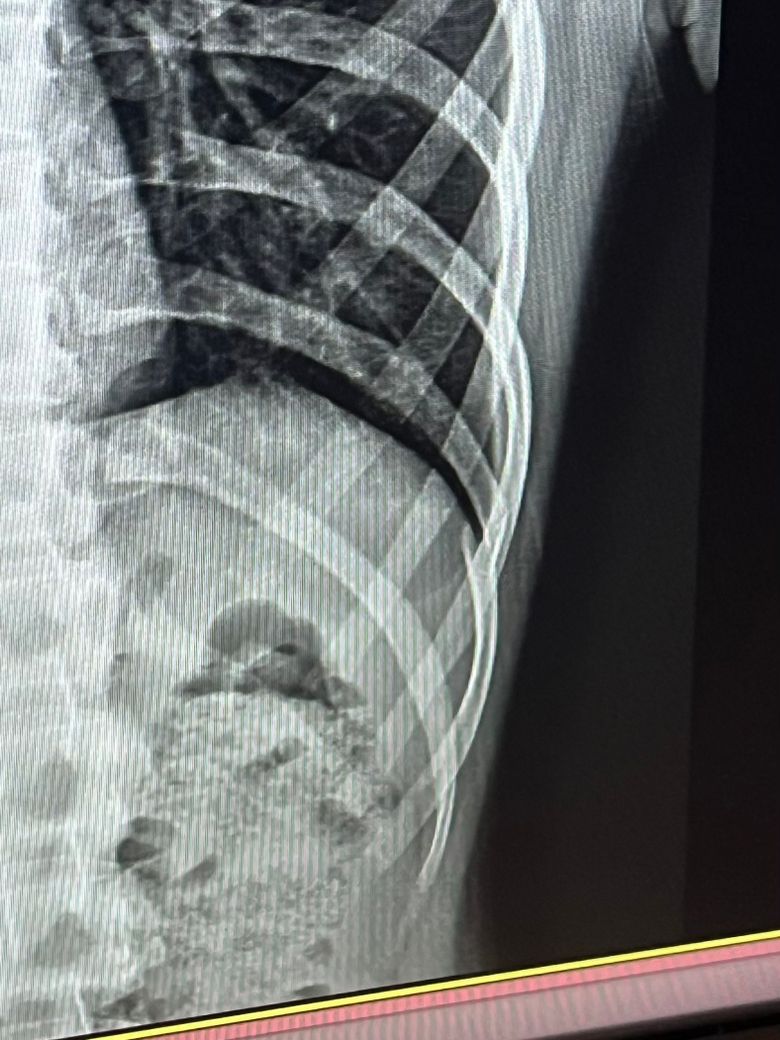

갈비뼈 골절 어긋남 수술 없어도 될까요? 사진 o

부딪혀서 갈비뼈가 부러졌는데 병원 문 닫는 시간에 가서 제대로 질문을 못 하구 나왔습니다 ㅜㅜ

어긋나서 부러졌다고 하셨는데 이런 경우 수술 없이 자연적으로 붙어도 합병증이 없을까요?

저렇게 어긋났는데도 뼈가 붙을 수 있나요 ? ㅠ ㅠ

갈비뼈 골절은 수술없이 잘 붙습니다 그러나 골절된 부위가 심하게 어긋나거나 인근 장기에 예를들어 폐같은 곳에 영향을 미칠 수 있는 경우에는 합병증이 발생할 수 있습니다 하지만 위의 사진으로봤을때는 그정도로 심해보이지 않습니다